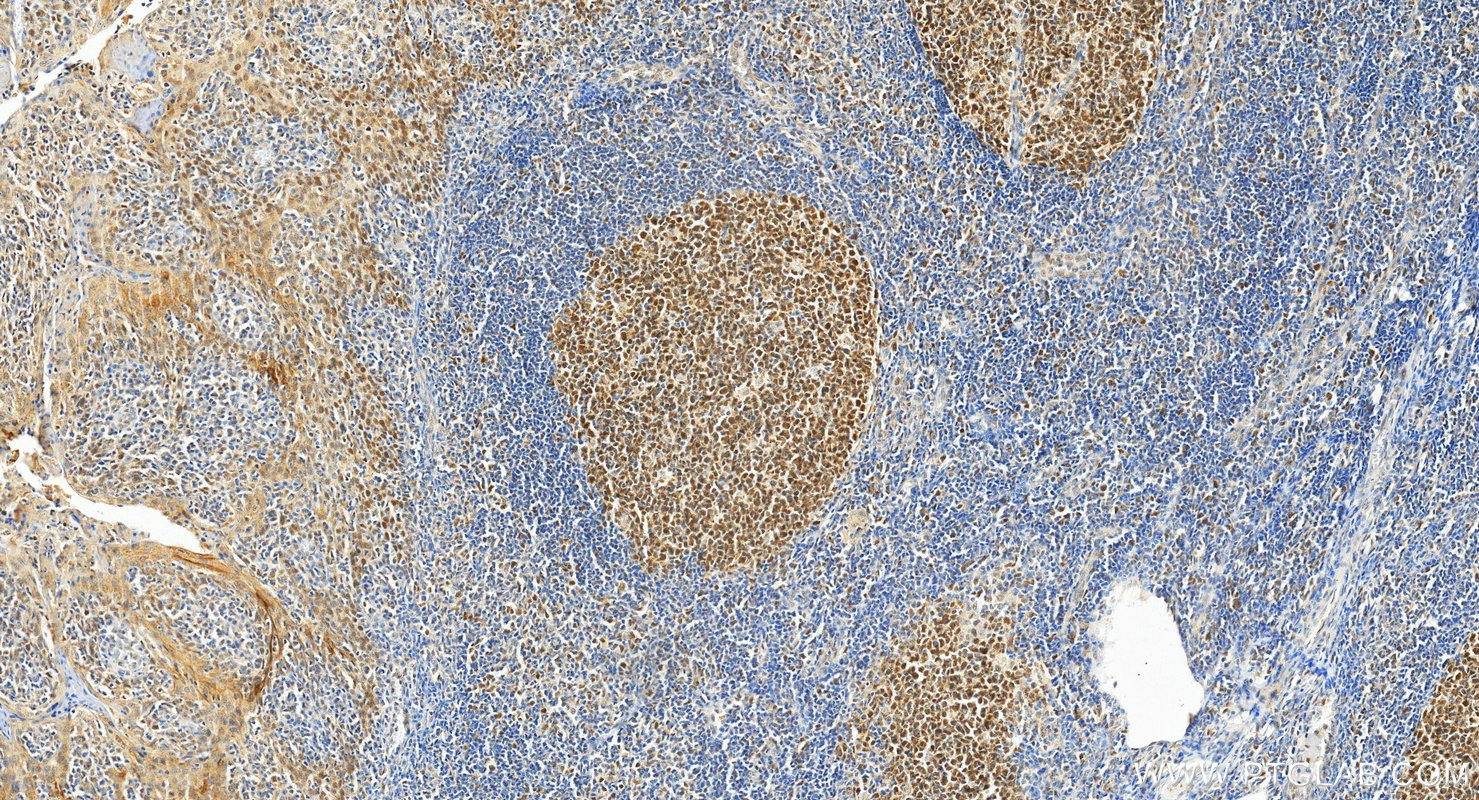

| Positive IHC detected in | human colon cancer tissue, human tonsillitis tissue, Ramos cells Note: suggested antigen retrieval with TE buffer pH 9.0; (*) Alternatively, antigen retrieval may be performed with citrate buffer pH 6.0 |

| Immunohistochemistry (IHC) | IHC : 1:500-1:2000 |